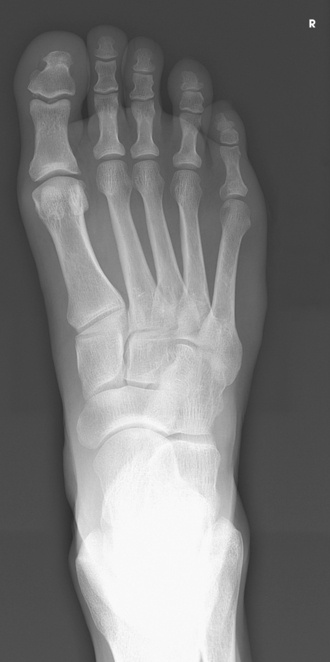

The foot consists of 26 bones (Figs. 6-1 and 6-2):

The bones of the foot are similar to the bones of the hand. Structural differences permit walking and support of the body’s weight. For descriptive purposes, the foot is sometimes divided into the forefoot, midfoot, and hindfoot. The forefoot includes the metatarsals and toes. The midfoot includes five tarsals—the cuneiforms, navicular, and cuboid bones. The hindfoot includes the talus and calcaneus. The bones of the foot are shaped and joined together to form a series of longitudinal and transverse arches. The longitudinal arch functions as a shock absorber to distribute the weight of the body in all directions, which permits smooth walking (see Fig. 6-2). The transverse arch runs from side to side and assists in supporting the longitudinal arch. The superior surface of the foot is termed the dorsum or dorsal surface, and the inferior, or posterior, aspect of the foot is termed the plantar surface.

The five metatarsals are numbered one to five beginning at the medial or great toe side of the foot. The metatarsals consist of a body and two articular ends. The expanded proximal end is called the base, and the small, rounded distal end is termed the head. The five heads form the “ball” of the foot. The first metatarsal is the shortest and thickest. The second metatarsal is the longest. The base of the fifth metatarsal contains a prominent tuberosity, which is a common site of fractures.

Beneath the head of the first metatarsal are two small bones called sesamoid bones. They are detached from the foot and embedded within two tendons. These bones are seen on most adult foot radiographs. They are a common site of fractures and must be shown radiographically (see Fig. 6-2).